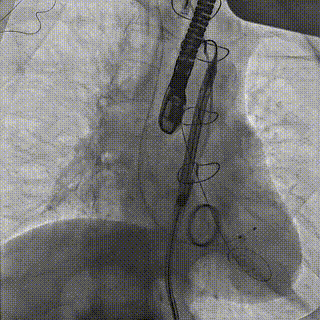

Step 2.输送系统过弓:4.4mm极细入路丝滑通过,柔顺过弓

6.gif